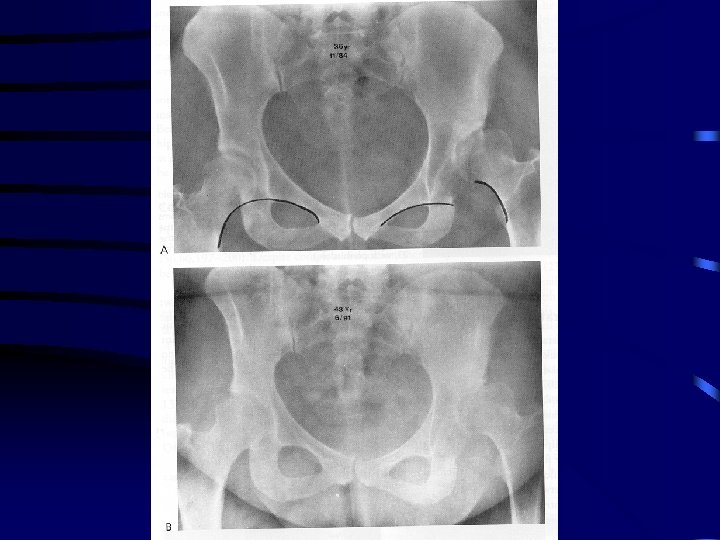

Adults • Variable • depends on 2 factors – well developed false acetabulum ( 24 % chance good result vs 52 % if absent) – bilaterality • in absence of false acetabulum patients maintain good ROM with little disability • femoral head covered with thick elongated capsule • false acetabulum increases chances degenerative joint disease • hyperlordosis of lumbar spine assoc with back pain • unilateral dislocation has problems – leg length inequality, knee deformity , scoliosis and gait disturbance

Dysplasia and Subluxation • Dysplasia (anatomic and radiographic def’n) – inadequate dev of acetabulum, femoral head or both – all subluxated hips are anatomically dysplastic • radiologically difference between subluxated and dysplastic hip is disruption of Shenton’s line – subluxation: line disrupted, head is superiorly, superolaterally ar laterally displaced from the medial wall – dysplasia: line is intact • important because natural history is different

Natural History Con’t • Subluxation predictably leads to degenerative joint disease and clinical disability – mean age symptom onset 36. 6 in females and 54 in men – severe xray changes 46 in female and 69 in males • Cooperman – 32 hips with CE angle < 20 without subluxation – 22 years all had xray evidence of DJD – no correlation between angle and rate of development – concluded that radiologically apparent dysplasia leads to DJD but process takes decades

Adolescent or Adult • Femoral osteotomy should only be used in conjunction with pelvic procedure as no potential for acetabular growth or remodeling but changing orientation of femur shifts the weightbearing portion • Pelvic osteotomy considerations – age – congruent reduction – range of motion – degenerative changes

Pelvic Procedures • Redirectional – Salter ( hinges on symphysis pubis) – Sutherland double innominate osteotomy – Steel ( Triple osteotomy) – Ganz ( rotational) • Acetabuloplasties ( decrease volume ) – hinge on triradiate cartilage ( therefore immature patients) – Pemberton – Dega ( posterior coverage in CP patients ) • Salvage – depend on fibrous metaplasia of capsule – shelf and Chiari